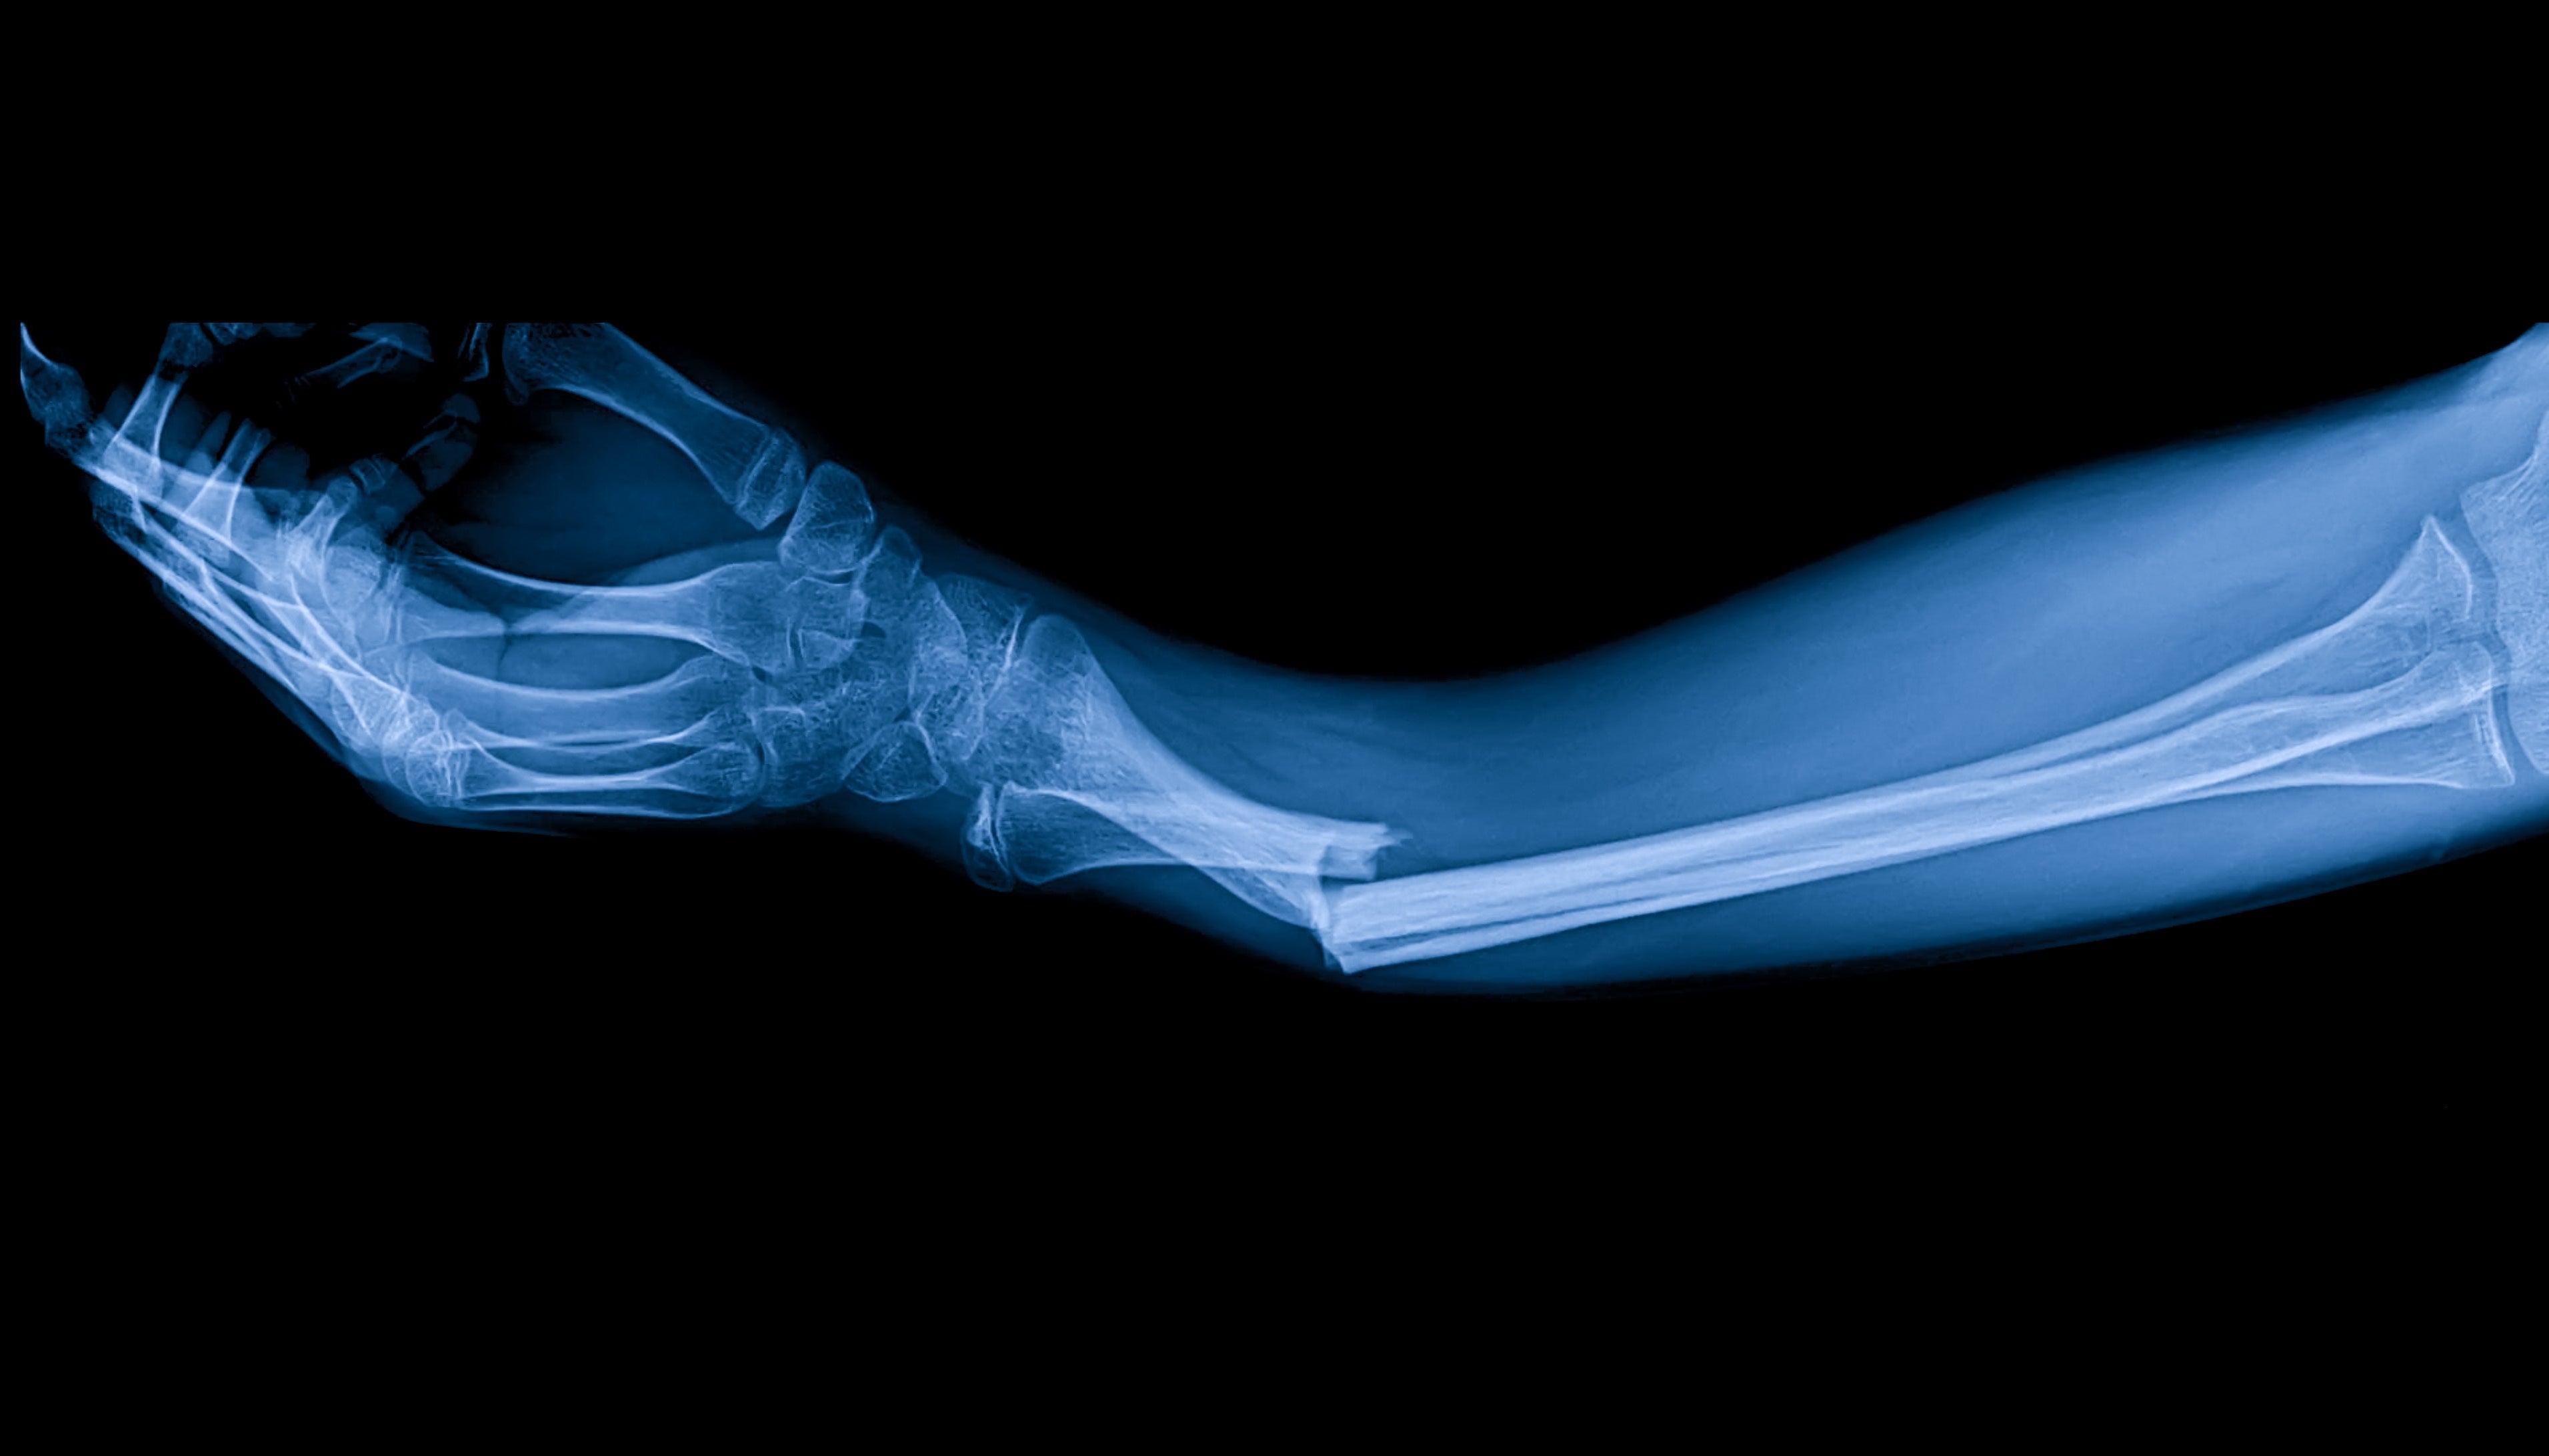

Les fractures osseuses peuvent résulter d'accidents, de chutes ou de blessures sportives, et nécessitent une période de rétablissement importante qui varie en fonction de la gravité et de la localisation de la fracture. Les méthodes traditionnelles de guérison des os comprennent l'immobilisation avec des plâtres ou des attelles, et parfois des interventions chirurgicales. La thérapie PEMF complète ces méthodes en stimulant la réparation cellulaire et la croissance osseuse au niveau moléculaire.